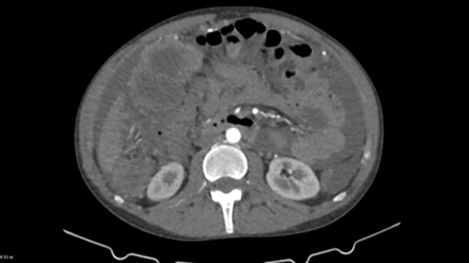

Following an ultrasound examination which revealed hypoechoic heterogeneous

masses, a contrast-enhanced computed tomography (ct) scan yielded mild ascites

and significant opacity of the peritoneal fat, along with heterogenous focal

lesions. The largest mass was located in the lesser pelvis, measuring 20 x 14.5

x 16 cm, accompanied by concurrent enhancement in the paracolic gutters and

omentum, indicating further peritoneal dissemination (figure 1a and 1b).

Figure 1a

& 1b: preoperative

contrast enhanced ct scan of the largest lesion measuring 20 x 14.5 x 16 cm.